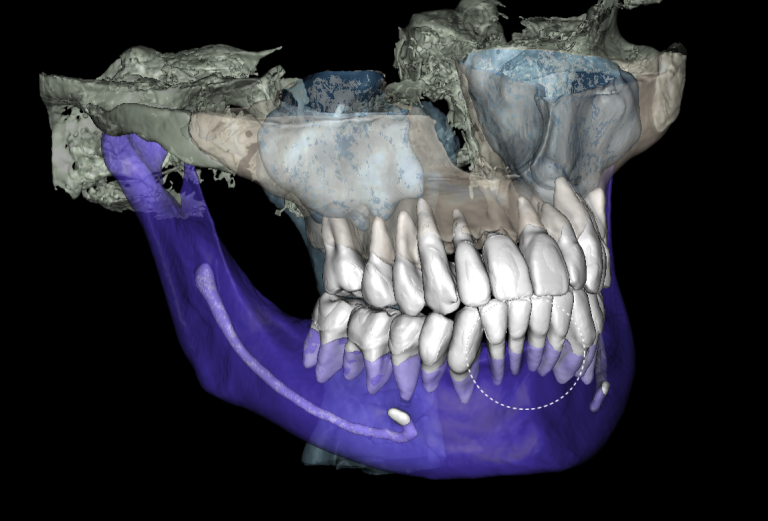

Solution: Diagnocat’s reports, based on CBCT and intraoral scans (STL files), help the clinician to quickly and accurately make decisions about treatment tactics and final tooth position, and to plan comprehensive treatment according to the individual needs of the patient